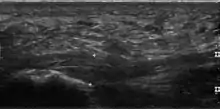

Plantar fasciitis is usually diagnosed by a health care provider after consideration of a person's presenting history, risk factors, and clinical examination.[4][17][18] Palpation along the inner aspect of the heel bone on the sole may elicit tenderness during the physical examination.[4][11] The foot may have limited dorsiflexion due to excessive tightness of the calf muscles or the Achilles tendon.[7] Dorsiflexion of the foot may elicit the pain due to stretching of the plantar fascia with this motion.[4][12] Diagnostic imaging studies are not usually needed to diagnose plantar fasciitis.[7] Occasionally, a physician may decide imaging studies (such as X-rays, diagnostic ultrasound, or MRI) are warranted to rule out serious causes of foot pain.

Medical imaging is not routinely needed. It is expensive and does not typically change how plantar fasciitis is managed.[15] When the diagnosis is not clinically apparent, lateral view X-rays of the ankle are the recommended imaging modality to assess for other causes of heel pain, such as stress fractures or bone spur development.[7]

The plantar fascia has three fascicles-the central fascicle being the thickest at 4 mm, the lateral fascicle at 2 mm, and the medial less than a millimeter thick.[19] In theory, plantar fasciitis becomes more likely as the plantar fascia's thickness at the calcaneal insertion increases. A thickness of more than 4.5 mm ultrasound and 4 mm on MRI are useful for diagnosis.[20] Other imaging findings, such as thickening of the plantar aponeurosis, are nonspecific and have limited usefulness in diagnosing plantar fasciitis.[13]